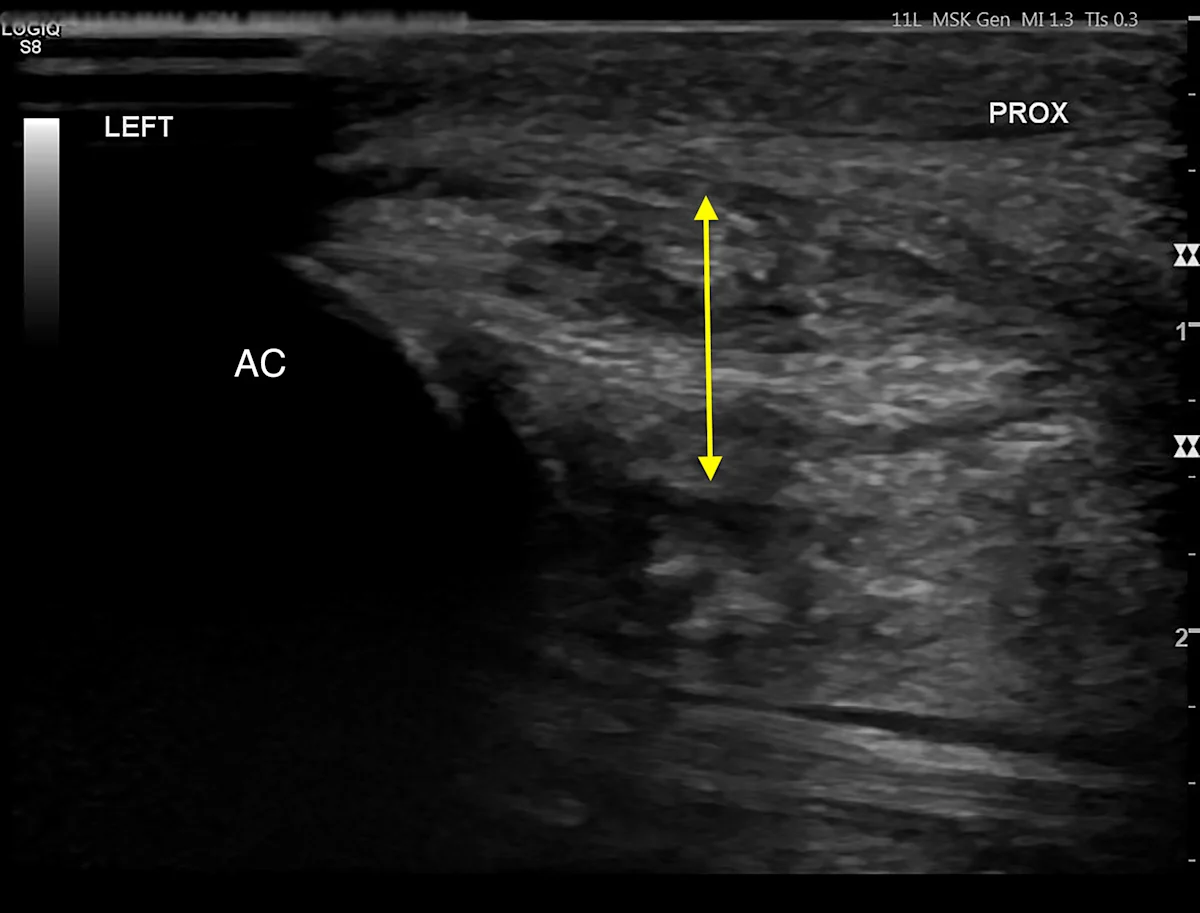

Based on the location of soft tissue swelling, a strain injury to the tendon of the flexor carpi ulnaris at the insertion on the accessory carpal bone was suspected. Musculoskeletal ultrasonography of the left and right antebrachium was performed for comparison and revealed significant tendon disruption of the insertions of the humeral and ulnar heads of the left flexor carpi ulnaris (Figure 3).8 Hyperechoic regions indicated fibrosis, which is typical of chronic injury.

Ultrasound images of the abnormal left flexor tendon (A) and contralateral normal right flexor tendon (B) at the insertion on the accessory carpal bone (arrows). The irregular fiber pattern and regions of hypoechoic and hyperechoic tendon in the left thoracic limb indicate tendon fiber disruption and fibrosis consistent with chronic injury. AC, accessory carpal bone